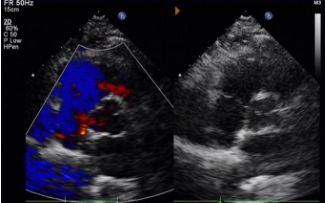

Today, we share a remarkable case highlighting 1-year post-op outcomes of MemoSorb in treating a complex long-tunnel PFO (12mm length, 1.4mm width), with a focus on serial echocardiographic evidence of device degradation and clinical symptom resolution.

Implant: 2424 MemoSorb®Biodegradowalny okluder PFO stosowany pod kierunkiem echa i DSA.

Dzień od 1 do 9 miesięcy:

Nie zaobserwowano szczątkowego bocznika.

Stopniowe zmniejszanie echogeniczności urządzenia.